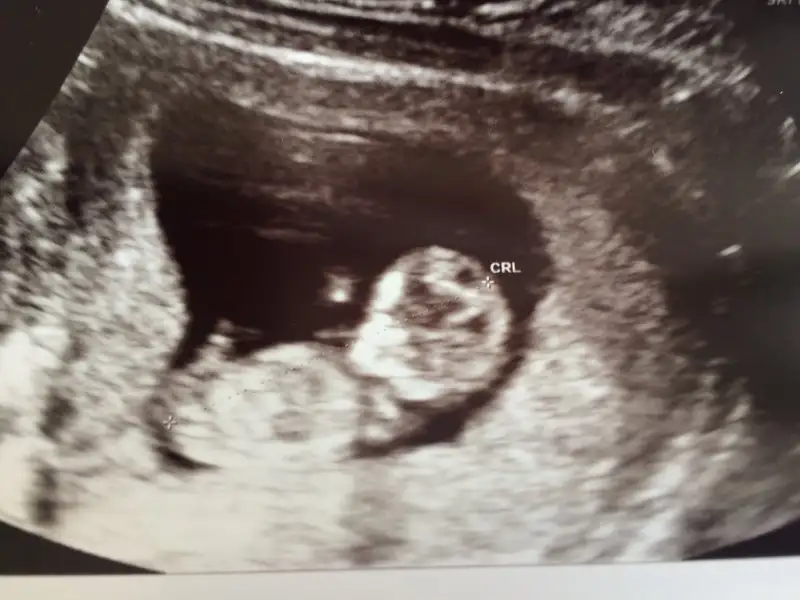

Maşallah canım. Çok güzel gözüküyor:) ben bilmiyorum ama nub teorisi yapan bir arkadaş vardı benim kızımı bilmişti kk da aratıp ona göster istersen :)Kızlaar ben geldim doktor kontrolünden çok şükür herşey sorunsuz. Gayet sağlıklıymış bebişimiz 4 cm olmuş kocaman bir bebek ya :). Müthiş bir duyguydu taklalar atıyor sürekli ters dönüyor kollar bacaklar hareketli video çekti eşim artık bir sonraki kontrole kadar sürekli izlerim. İkili test içinde 1 marta çağırdı. Ense kalınlığı şuan için çok iyi dedi. Normalde bugün 10+2'yim ama 10+6 çıktı önden gidiyormuş. Cinsiyet için yorum yapmadı ikili testte söylerim dedi. Bakalım çok heyecanlı darısı herkese güzel haberler almayı nasip etsin rabbim. Buraya resimde ekleyeyim bakalım cinsiyet tahmini yapabilecek varmı

Canım maşallah. Şu genital nuba göre bence kız gibi. Paralel görüyor nubuKızlaar ben geldim doktor kontrolünden çok şükür herşey sorunsuz. Gayet sağlıklıymış bebişimiz 4 cm olmuş kocaman bir bebek ya :). Müthiş bir duyguydu taklalar atıyor sürekli ters dönüyor kollar bacaklar hareketli video çekti eşim artık bir sonraki kontrole kadar sürekli izlerim. İkili test içinde 1 marta çağırdı. Ense kalınlığı şuan için çok iyi dedi. Normalde bugün 10+2'yim ama 10+6 çıktı önden gidiyormuş. Cinsiyet için yorum yapmadı ikili testte söylerim dedi. Bakalım çok heyecanlı darısı herkese güzel haberler almayı nasip etsin rabbim. Buraya resimde ekleyeyim bakalım cinsiyet tahmini yapabilecek varmı

Kızlaar ben geldim doktor kontrolünden çok şükür herşey sorunsuz. Gayet sağlıklıymış bebişimiz 4 cm olmuş kocaman bir bebek ya :). Müthiş bir duyguydu taklalar atıyor sürekli ters dönüyor kollar bacaklar hareketli video çekti eşim artık bir sonraki kontrole kadar sürekli izlerim. İkili test içinde 1 marta çağırdı. Ense kalınlığı şuan için çok iyi dedi. Normalde bugün 10+2'yim ama 10+6 çıktı önden gidiyormuş. Cinsiyet için yorum yapmadı ikili testte söylerim dedi. Bakalım çok heyecanlı darısı herkese güzel haberler almayı nasip etsin rabbim. Buraya resimde ekleyeyim bakalım cinsiyet tahmini yapabilecek varmı